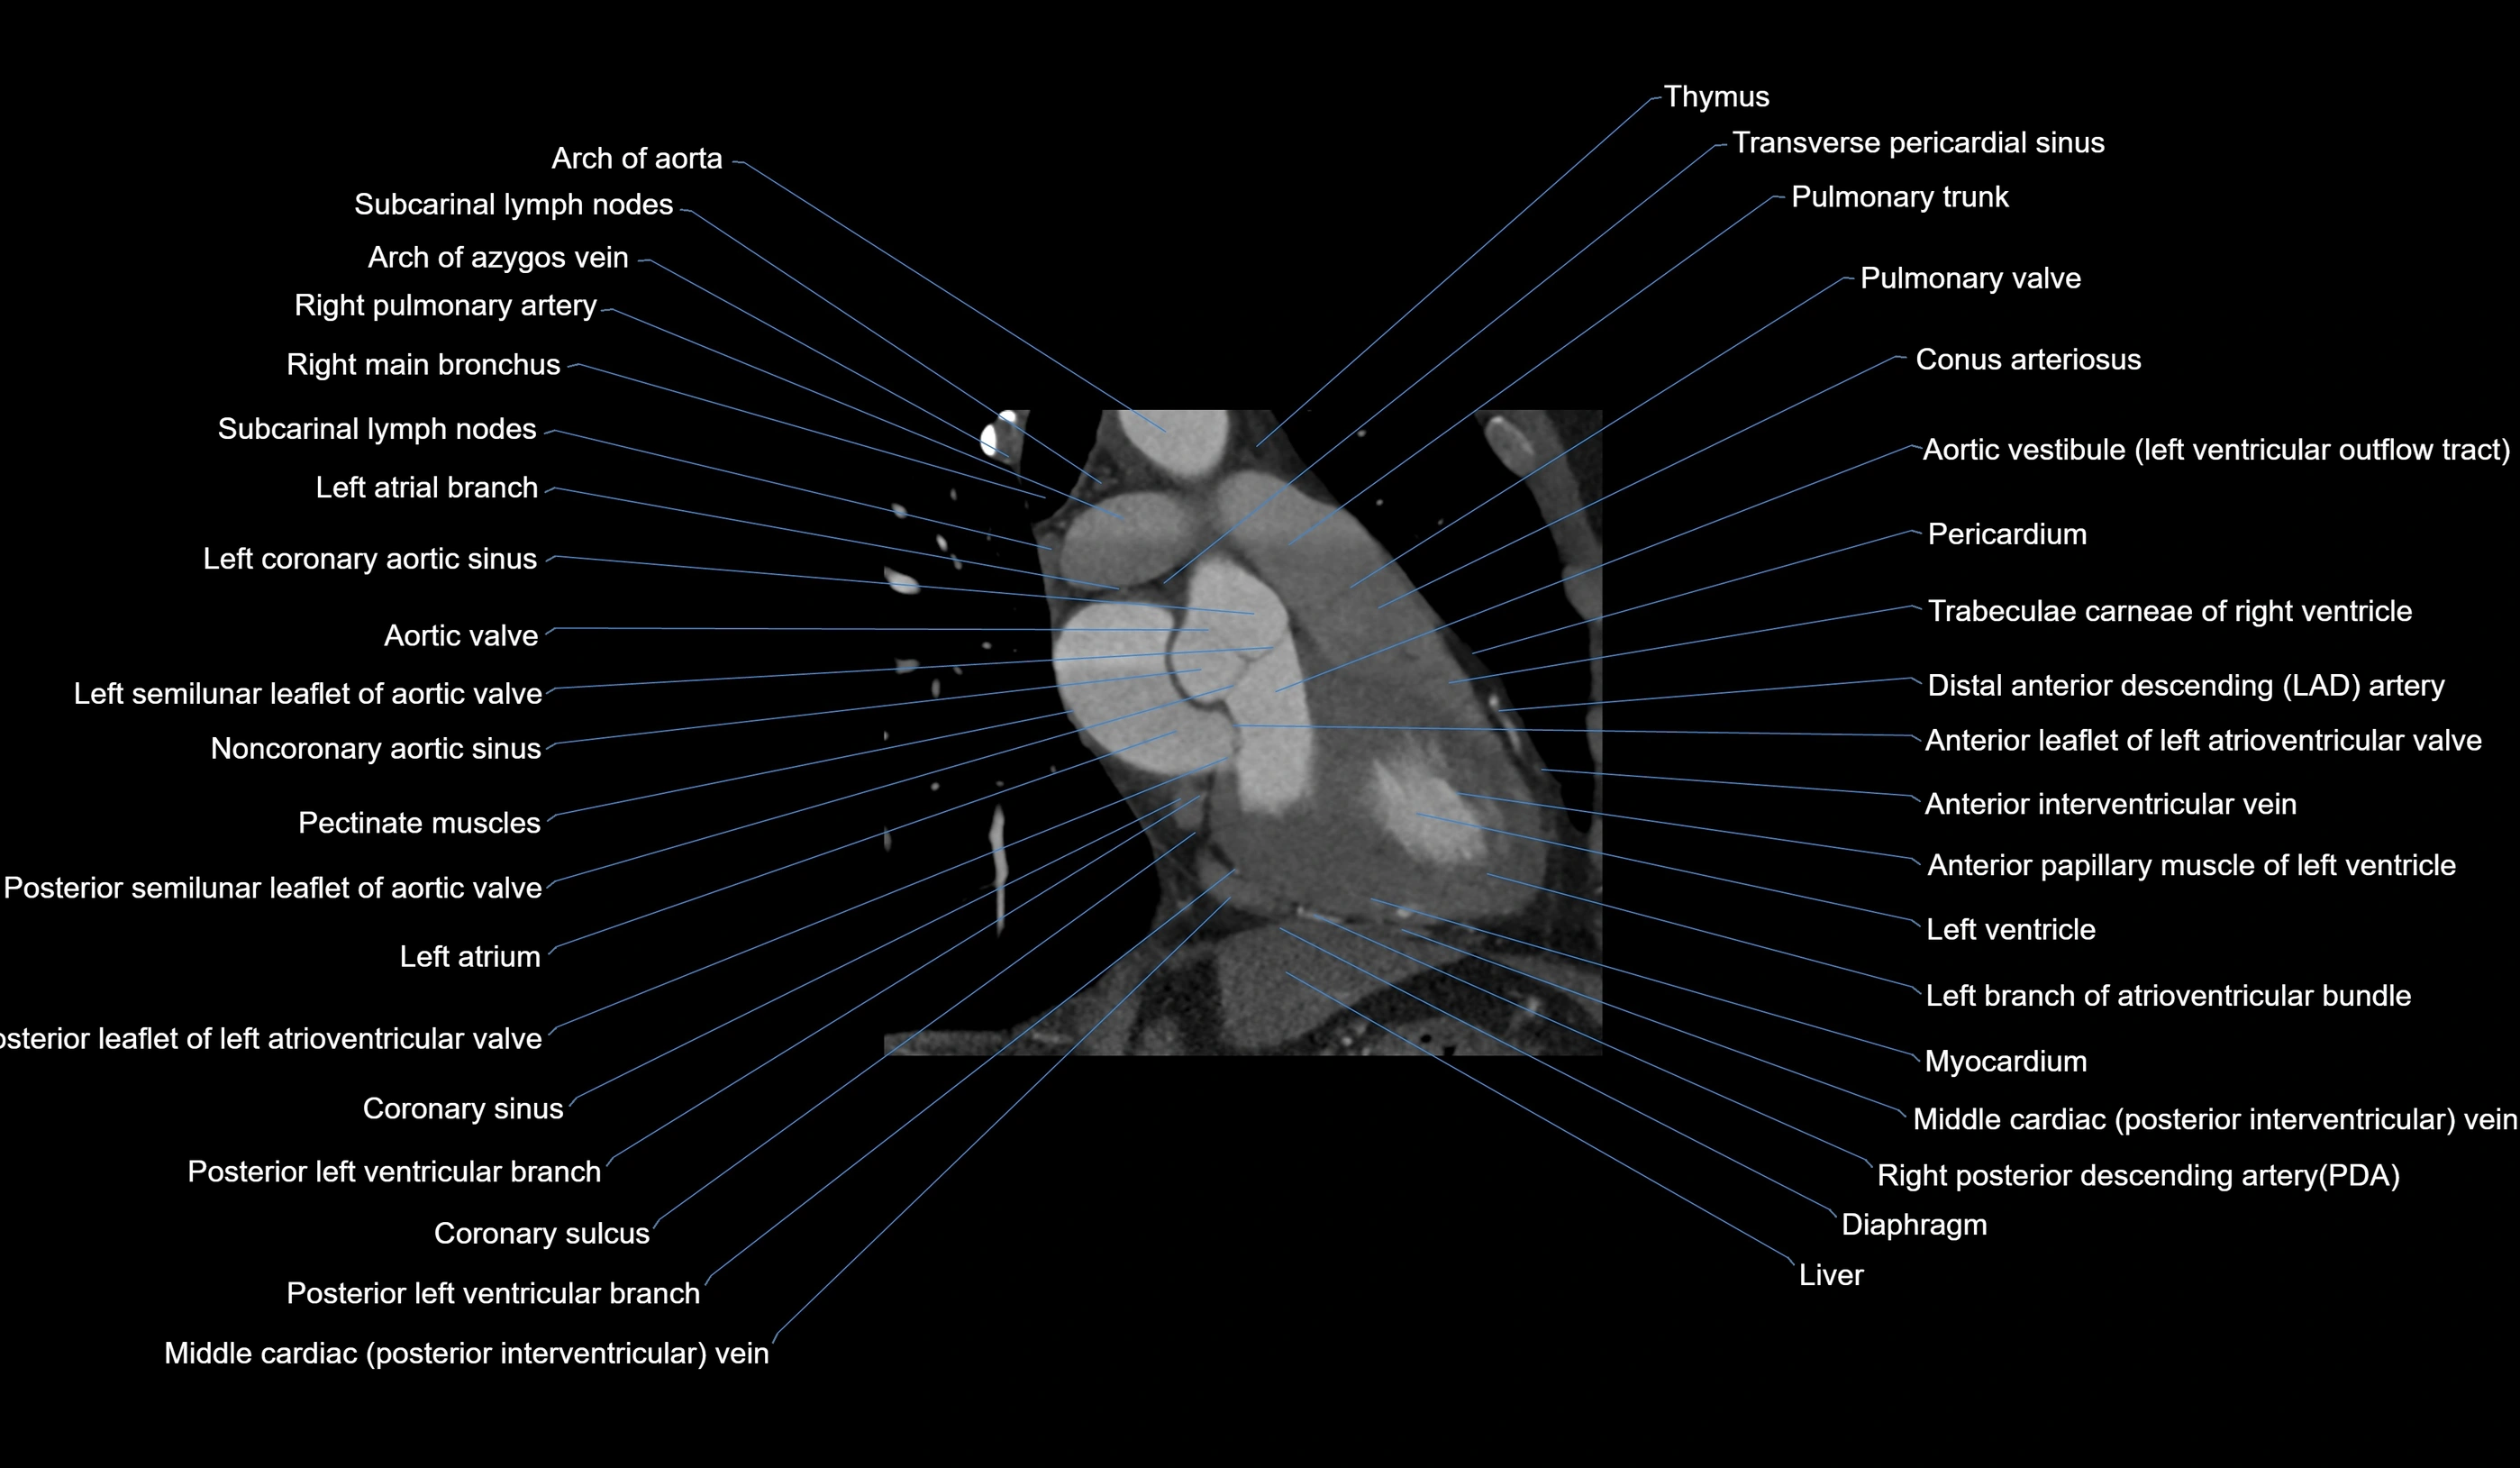

CT images